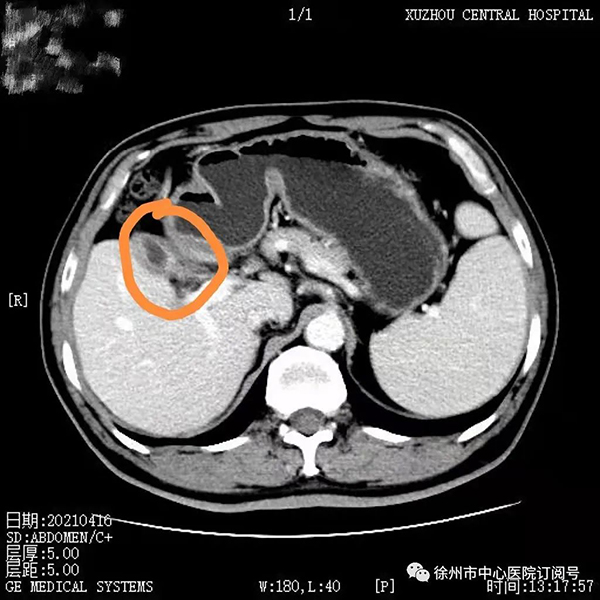

2020年8月,董先生行第一次靶免治療,無(wú)特殊不良反應(yīng),后間隔21天行一次治療至第4療程;2020年10月腹部CT檢查見(jiàn)腫瘤較前縮小,病情持續(xù)好轉(zhuǎn);2021年4月進(jìn)行第9療程再次復(fù)查腹部CT顯示,此時(shí)腫瘤較第一次治療時(shí)已明顯縮小。

2021年4月,第9療程腹部增強(qiáng)CT:膽囊癌復(fù)查,膽囊壁增厚毛糙,較之前無(wú)明顯變化。